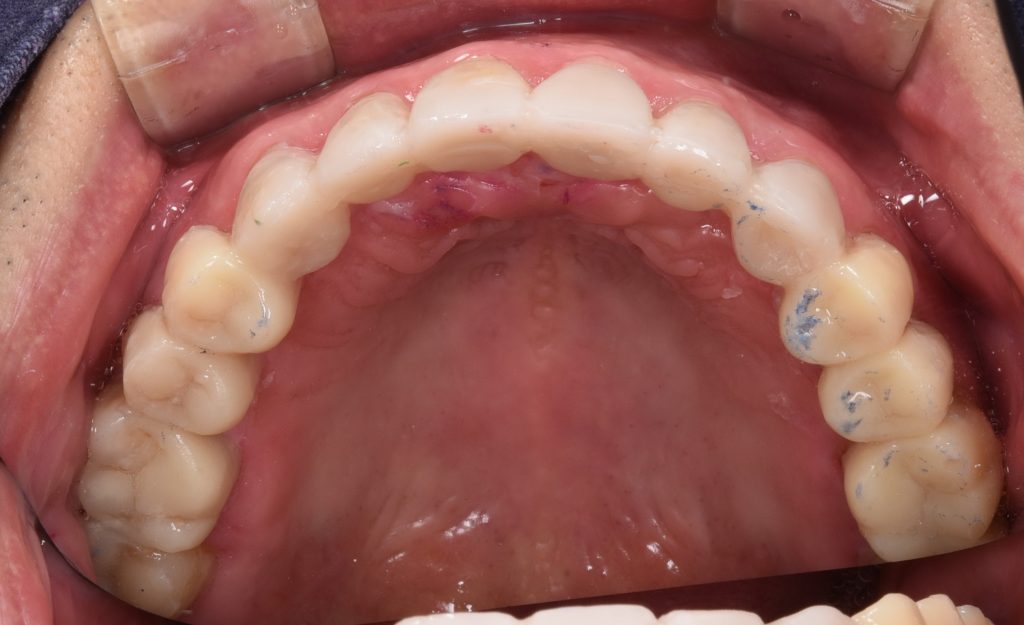

Iniital

initial photo with severe worn down dentition